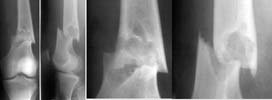

A male 17 years old fallen while usual walking. Images attached combining common and detailed view of the fracture area.

The images show something like a bone cyst. So the question is about preferred method of treatment. Can nailing be an option here? Or we should avoid any touch of the focus and use ex-fix only? Is biosy strongly needed? I would also greatly appreciate any common reference to a systematic review or common guide on surgical management of fractures over cysts, fibrous displasia etc.